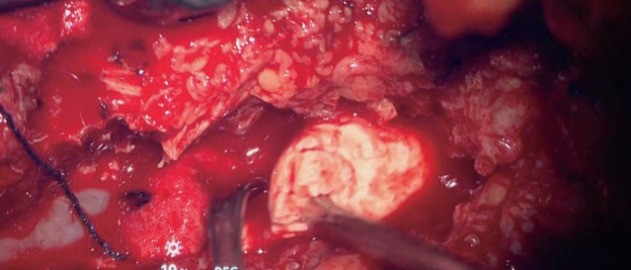

骨水泥增强椎弓根螺钉内固定是一种被广泛接受的治疗骨质疏松性骨折的方法,但它具有固有的风险,特别是与骨水泥泄漏和栓塞有关。本研究旨在分析一例水泥内固定术后并发症的临床病例,并对相关文献进行详细的复习。一名70岁的患者接受了L2-L4椎弓根螺钉内固定和聚甲基丙烯酸甲酯增强,导致水泥渗漏到椎管中并随后发生肺栓塞。经翻修手术和栓塞保守治疗后,患者病情稳定,表明保守治疗水泥栓塞是有效的。为了补充本病例,我们进行了全面的文献回顾,以探讨与骨水泥增强术相关的并发症的原因、预防和治疗。研究结果表明,尽管骨水泥增强椎弓根螺钉内固定仍然是治疗骨质疏松性骨折的主要技术,但通过适当的治疗方案,相关风险是可控的。本研究通过强调与骨水泥固定相关的风险和解决方案,从而有助于改善患者的预后和制定标准化的治疗指南,对医疗保健专业人员具有实际意义。

Cement-augmented pedicle screw instrumentation is a widely accepted method for managing osteoporotic fractures, but it carries inherent risks, particularly related to cement leakage and embolism. This study aimed to analyze a clinical case of complications following cement fixation and provide a detailed review of relevant literature. A 70-year-old patient underwent transpedicular screw instrumentation from L2-L4 with polymethyl methacrylate augmentation, which resulted in cement leakage into the spinal canal and subsequent pulmonary embolism. After revision surgery and conservative treatment for the embolism, the patient's condition stabilized, demonstrating that conservative measures can be effective in managing cement embolism. To complement this case, a comprehensive literature review was conducted to explore the causes, prevention, and treatment of complications related to cement augmentation. The findings support that while cement-augmented pedicle screw instrumentation remains a leading technique for osteoporotic fractures, the associated risks are manageable with proper treatment protocols. This study holds practical significance for healthcare professionals by highlighting both the risks and solutions associated with cement fixation, thus contributing to improved patient outcomes and the development of standardized treatment guidelines.